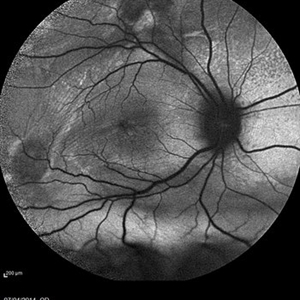

VOGT KOYANAGI HARADA

Oct 7 2015 by Avris Romario Diparaja Siahaan

Fundus photograph of a 42-year-old woman with a Harada Syndrome in both eyes.

Photographer: Avris Romario Diparaja Siahaan, Klinik Mata Nusantara

Imaging device: Topcon TRC 50DX IA

Condition/keywords: color fundus photograph, Vogt-Koyanagi-Harada